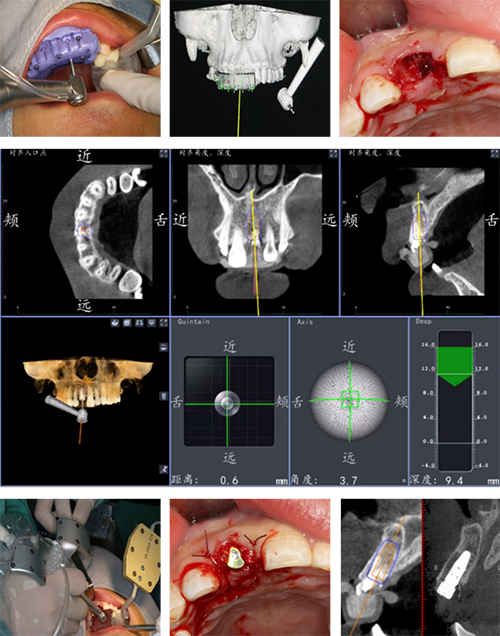

术中,首先安装并配准导航设备,微创拔除患牙残根后,在数字化全程导航引导下,按照术前设计位点和植入方向、深度,成功完成种植体精准植入。术后,患者CBCT结果显示种植体植入位置及深度与术前设计一致,证实了国产数字化动态种植导航系统的临床应用价值。

黄圣运介绍,前牙美学区即刻种植因剩余骨量和拔牙窝形态结构问题,手术操作精度要求高,自由手操作的误差可能造成种植体植入初期稳定性差,美学效果不理想,最终导致前牙美学修复失败。数字化动态种植导航通过术前最优化种植设计,利用实时、动态术中定位,在手术中实现术者-患者-种植机同步协调,完成自由手无法完成的精准种植操作。作为国内首批国产数字化动态种植导航系统的临床推广单位,本次数字化种植手术的成功是我院在种植领域微创化、先进化、精准化的又一重要进展。